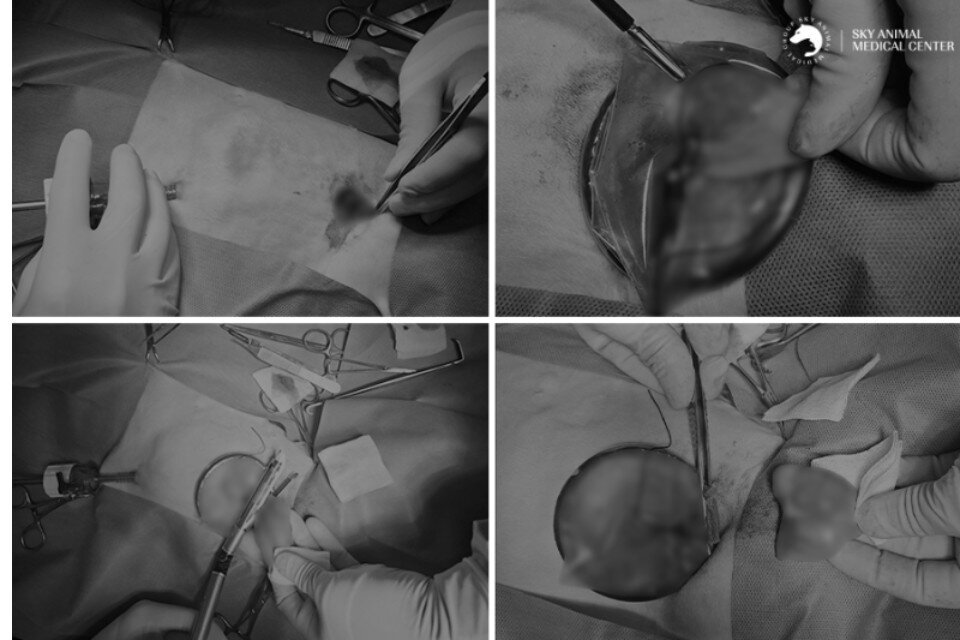

본문 이미지 - 개흉 범위를 최소화하고, 통증·감염·조직 손상 위험을 줄이기 위해 흉강경을 이용해 수술하는 모습(동물병원 제공) ⓒ 뉴스1

개흉 범위를 최소화하고, 통증·감염·조직 손상 위험을 줄이기 위해 흉강경을 이용해 수술하는 모습(동물병원 제공) ⓒ 뉴스1